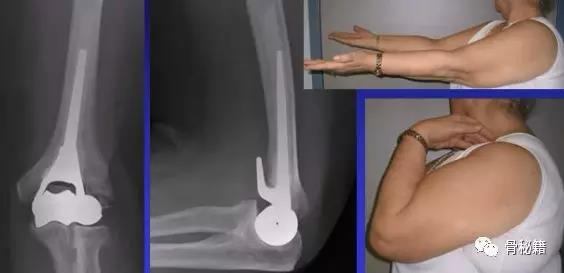

实在固定不了的时候,再进行肘关节置换术肘关节又分为半肘和全肘

术后早期康复

除了非常罕见的病例外,所有患者在手术后24小时开始被动和主动运动,需要保留在弹性绷带中,同时限制过度的运动。在手术后三周,在移除缝线时移除弹性绷带。患者被告知不能负重,直到发生骨愈合。